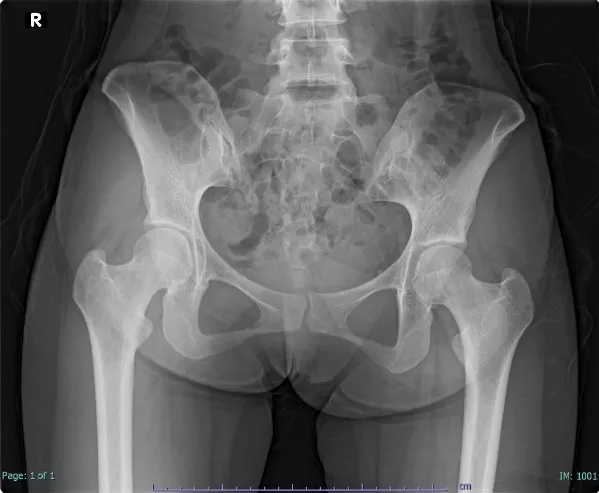

| <症例> | 20代女性 |

| <主訴> | 左臀部痛 |

現病歴

診察所見

独歩で来院。皮膚や爪などに異常所見はなく、四肢関節腫脹圧痛はなかった。体温36.7℃。左臀部に圧痛があった。

写真1